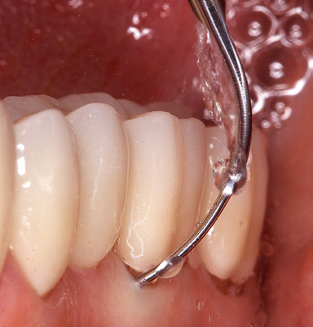

Das aktuelle Arbeitskonzept für die UPT

Die Aktualisierung der Anamnese stellt im Rahmen der UPT eine zentrale Maßnahme dar, sie sollte mindestens einmal jährlich erfolgen. Sie dient dazu, mögliche neue Risikofaktoren zu erkennen und zu dokumentieren. Vor allem dann, wenn ein Patient langjährig betreut wird, ist es wichtig, zu erfahren, ob sich patientenspezifische und allgemeinmedizinische Risikofaktoren verändert haben. Hier sollte an erster Stelle an ein erhöhtes Risiko durch Diabetes gedacht werden, aber auch andere allgemeinmedizinische Erkrankungen (kardiovaskuläre Erkrankungen und Neoplasien) können aufgrund der erfolgten Therapien und der notwendigen Medikamenteneinnahme zu einem veränderten Risikoprofil führen. Das Update der Anamnese ist also auch im Rahmen der UPT sehr wichtig, um gegebenenfalls aufgrund eines veränderten Risikoprofils eine Veränderung des Behandlungsintervalls zu veranlassen. Im nächsten Schritt ist es wichtig, der Diagnostik besondere Aufmerksamkeit zu schenken. Die Instrumentation ist zwar ein zentraler Bestandteil der UPT, in keinem Fall sollte sie aber Bestandsaufnahme und Dokumentation verdrängen. Für die Diagnose ist dabei der parodontale Befund unerlässlich, eine Zunahme der Sondierungstiefen und eine Erhöhung des BOPIndex sind zentrale Indikatoren für eine Progression parodontaler und periimplantärer Erkrankungen. Zum Erheben der benötigten Daten darf daher nicht davor zurückgeschreckt werden, auch Implantate zu sondieren. Dabei ist es wichtig, dass hierfür millimeterskalierte PARSonden verwendet werden. Für die Sondierungsbefunde an natürlichen Zähnen haben sich seit Jahrzehnten metallische Sonden bewährt. Bei Implantaten ist die Herausforderung für das Erheben korrekter und reproduzierbarer Sondierungsbefunde größer. Da es durch die Diskrepanz von Implantatdurchmesser und Kontur der Suprakonstruktion regelmäßig zu einer Überkonturierung der Suprastruktur kommt, sind für Sondierungen an Implantaten flexible, aber dennoch millimeterskalierte Son den sehr sinnvoll (z. B. Colorvue Kit PCV11KIT6, HuFriedy; Abb. 4).

Das Erheben eines kompletten PAR Status sollte bei Patienten ohne besondere Risikofaktoren mindestens einmal pro Jahr erfolgen. Bei Vorliegen mehrerer Risikofaktoren (Diabetes, Rauchen etc.) kann ein engmaschigeres Monitoring (halbjährlich) sinnvoll sein.